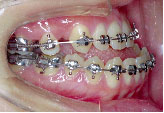

クォードヘリックスで上顎歯列を左右へ拡げた後、右上第1小臼歯を抜歯し、エッジワイズブラケットを付けて術前矯正を始めました。

骨の中に埋まっている左上の第2小臼歯は手術の時に抜いてもらいます。

術前矯正が終わりました。一見きれいになったようですが下あごはまだ左にずれたままです。